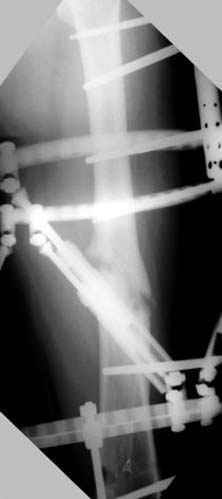

На рисунке N1 предоперационный план лечения ложного сустава шейки бедра- линия ложного сустава, угол и направление введения импланта, клиновидная остеотомия в градусах и миллиметрах, второй снимок после коррекции, расчет, на сколько удлиняется конечность и размеры импланта;

N3 рисунок окончательный снимок, после операции моя рентгенограмма должен выглядеть примерно как эта картина. На N4 снимке клин перед удалением; N5 послеоперации 3 нед.; N6 окончательная рентгенограмма.

варус при проксимальном отделе 95 градусной пластиной.

пластическая модель; и коррекция бедра аппаратом Илизарова.

Имею другие снимки тоже, получится как отчет о моей работе.